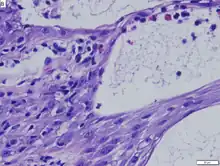

| Bullous arthropod assault | |

Arthropod assault is a medical term describing a skin reaction to an insect bite characterized by inflammation and eosinophilic response.[1]